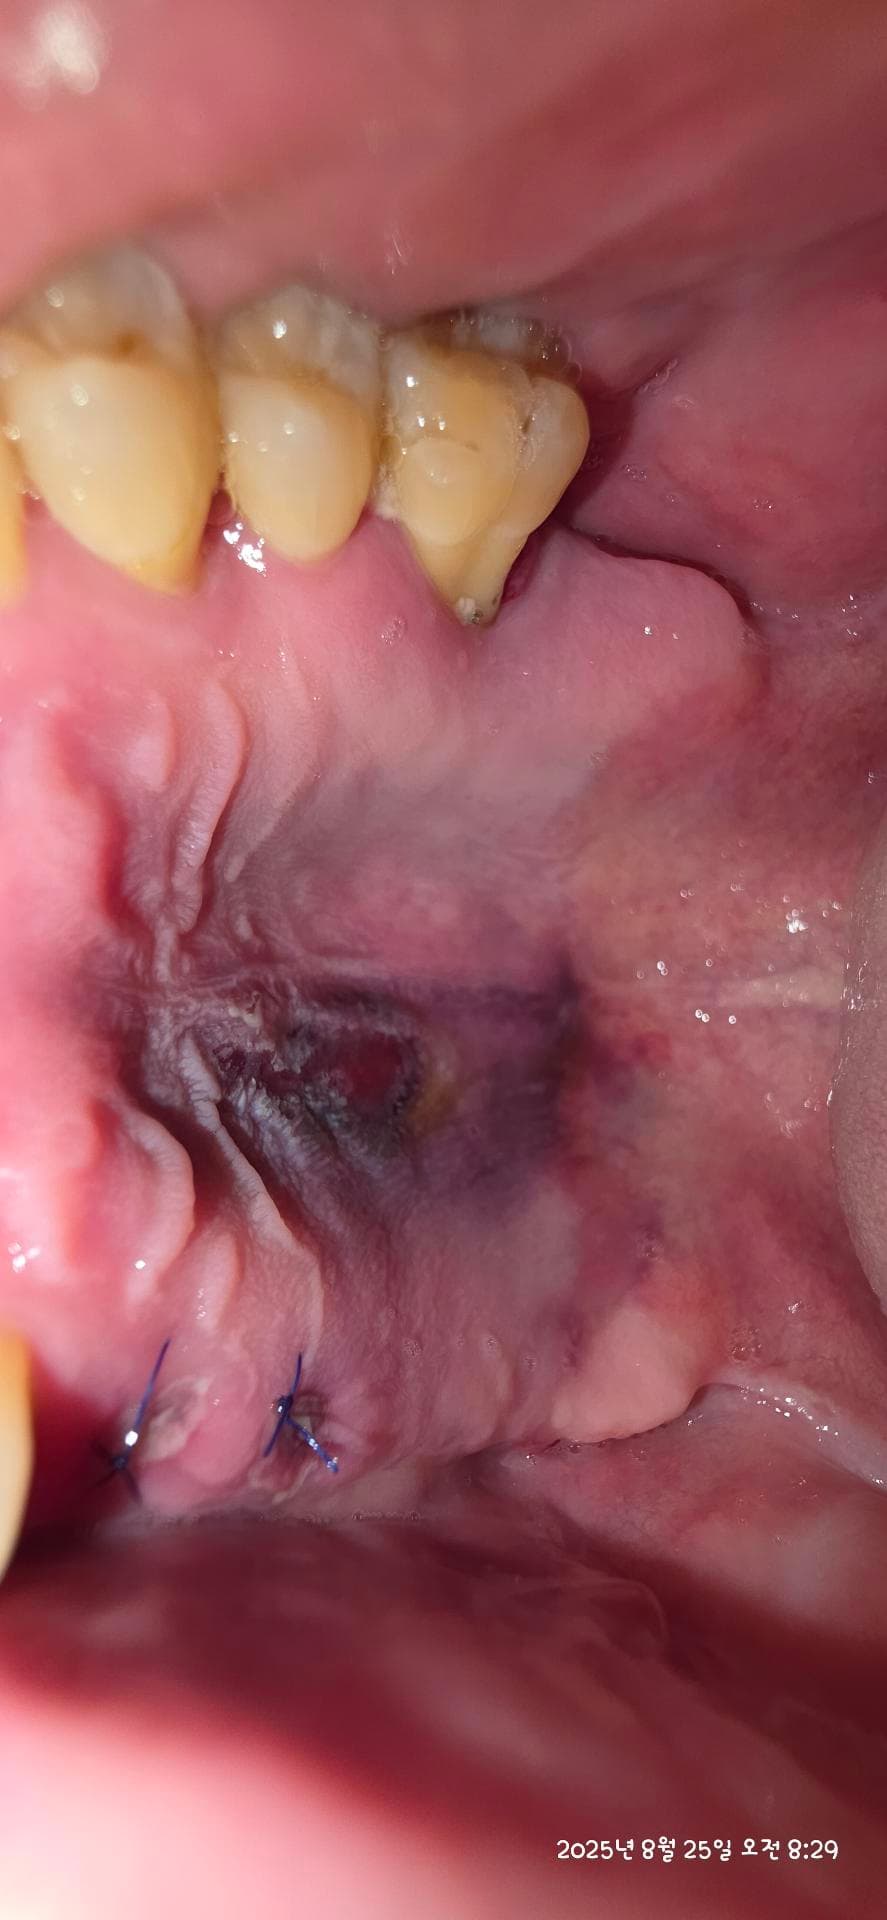

인플란트 식립하고와서 보니 입천장이 저렇게 되어있습니다. 이전에도 이랬던 것 같은데 이러는 이유가 뭘까요? 지금은 입천장 까진 것 과 비슷한 통증느껴 집니다

임플란트 식립시 입천장이 눌려서 생긴 멍자국같습니다 시야 확보를 위해서 당기거나 눌리면 피가 뭉쳐서 그럴수 있습니다.

임플란트 수술을 하게 되면 출혈이 되어 내부에 사진처럼 멍이 들수 있습니다. 멍은 2~3주정도 지나면 줄어들게 되며 통증이 있다면 처방된 진통제를 복용하는것이 좋습니다.